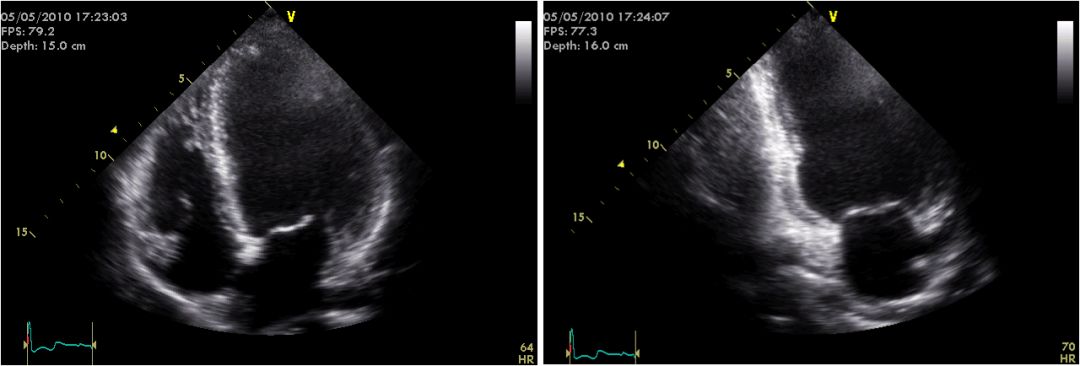

冠脉造影:右冠轻度动脉硬化,前降支、回旋支大致正常

超声心动图:双平面法LVEF48%,左心室心尖部、后壁中下部运动减弱,心尖部变薄)。左心室增大。轻度二尖瓣关闭不全,左冠状动脉7.5mm, 右冠状动脉8mm

三支病变